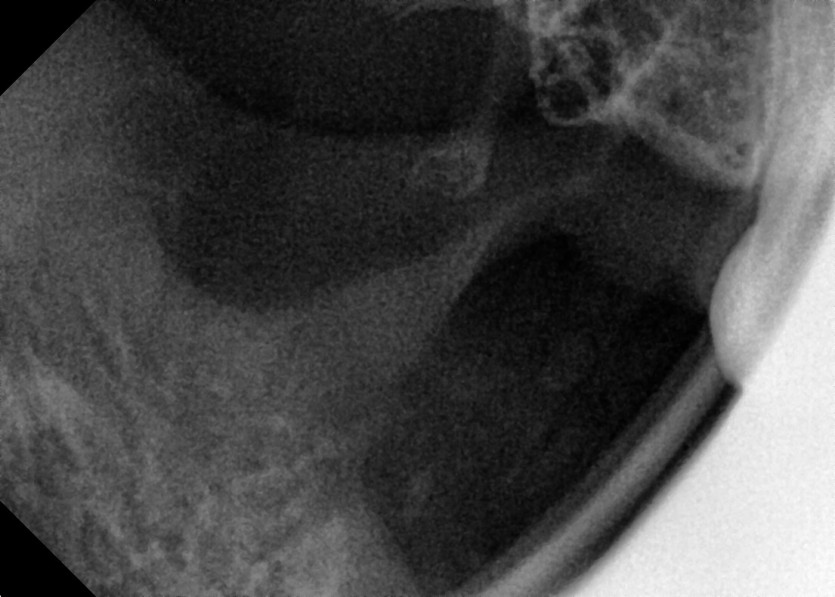

#18,28,38,48 사랑니 발치

구강 외과 전문의가 당일 발치했습니다.